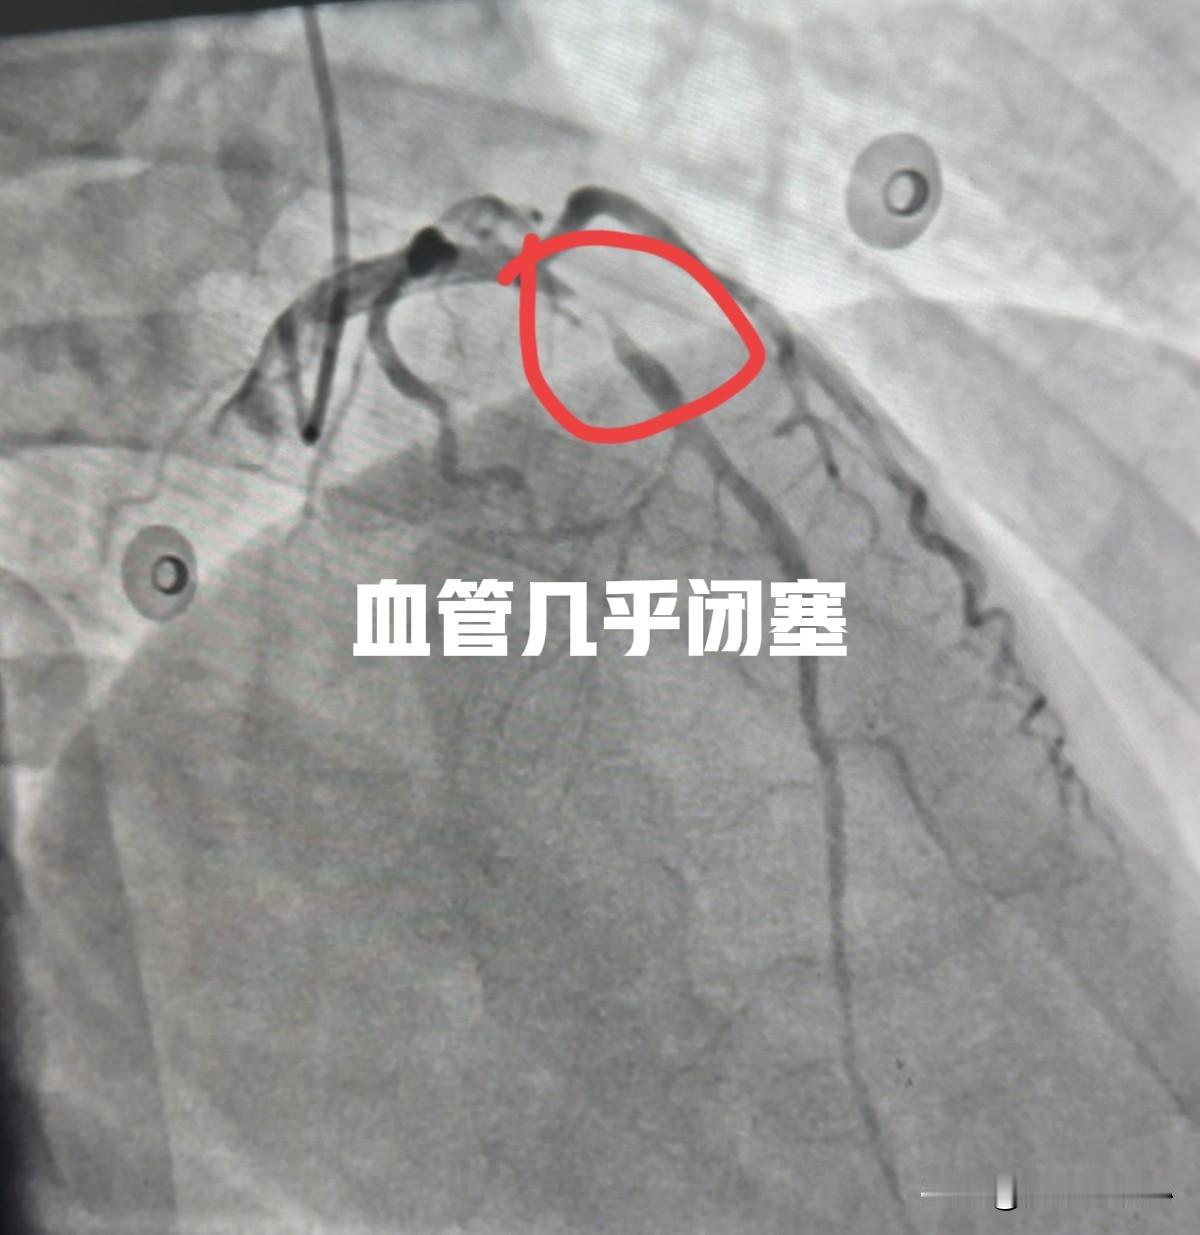

40 岁女性,最近 1 周出血剑突下疼痛,就是心口窝那里,持续性疼痛,开始以为是胃病,吃了胃药不见好,到医院看病,查了肌钙蛋白发现明显升高,心电图也有 T 波倒置的情况。经常看科普的朋友知道,这是心肌受损的表现。那是什么原因引起的心肌受损呢? 40 岁女性,年龄不大,且有女性雌激素保护作用,得冠心病可能性小。那难道是心肌炎?患者查血发现白细胞很高,是正常值的 1.5 倍,但患者没有发热、没有咳嗽、咳痰,没有腹泻等常见感染的表现。 患者转到我这里以后,再次复查心电图发现,前壁导联的 ST 段明显抬高了,典型的 ST 段抬高型心肌梗塞,但患者此时无任何胸痛症状,很轻松躺在病床上刷着手机。 安全起见,还是给患者做了急诊冠脉造影检查,结果发现前降支近段几近于闭塞,仅有一丝血流给心脏供血,非常危急,一旦血流中断,患者极有可能出现心脏骤停。立即球囊扩张开闭塞的部分,植入 2 枚支架后,狭窄解除。 很多人会有疑问,为什么这么年轻女性,冠状动脉狭窄这么严重?其实这个患者有长期的高血压和糖尿病,尤其是糖尿病血糖没有用药控制,糖化血红蛋白长期在 10 以上,血糖控制非常差。 高血压、糖尿病、高血脂这三高是冠心病、急性心肌梗塞最常见也是最重要的危险因素。很多人问该如何尽量降低冠心病风险,最简单也是最有效的方法就是控制好三高,不抽烟,就可以避免很大部分的冠心病了。